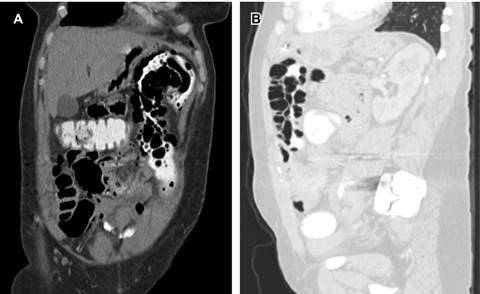

Aunque inicialmente fue descrita en 1730 por el patólogo francés DuVernoy, fue hasta 19251 cuando Mayer la nombró como neumatosis intestinal; también se le conoce, entre otras denominaciones, como pneumatosis coli, enfisema intestinal o buloso.2-4 Se trata de una patología de curso benigno, cuya incidencia es de 0.03% en la población1 y afecta más fecundamente a los varones (3.5:1)5, con una mayor presencia entre los 41 y 50 años.2,3 Se caracteriza por lesiones quísticas con gas en su interior, a nivel de las paredes del intestino delgado y grueso,2,3 entre las capas de la mucosa, submucosa o serosa.4 Los quistes subserosos son más frecuentes en los casos que involucran el intestino delgado, en tanto que, si afectan las paredes del colon, se conoce como pneumatosis coli, y se asocia con quistes submucosos.2,4 La presencia de neumoperitoneo se debe a la ruptura de dichos quistes (Figura 2).5 En 42% de los casos, éstos se asientan en las paredes del colon, 36% en el intestino delgado (yeyuno e íleon) y 22% tanto en el intestino grueso como en el delgado.2,3

Figura 2: Reconstrucción coronal (A) abdominal, en la que se destaca la presencia de burbujas de aire en las paredes del colon transverso y descendente, y reconstrucción sagital con ventana para pulmón (B), que muestra el signo de “racimos de uvas” formado por burbujas de aire en las paredes del colon.

La hipótesis más aceptada acerca de su fisiopatología es la teoría mecánica, la cual expone que existe paso de aire a través de la mucosa intestinal dañada, secundaria al aumento de presión intraluminal. Dicha teoría apoya la relación de la neumatosis intestinal con patologías que alteran la integridad de la mucosa, como la isquemia.2-4,6 Con la radiografía simple de abdomen, se pueden observar múltiples imágenes quísticas de la pared delgada, llenas de gas dentro de la pared intestinal, en patrón de “racimos de uvas”.4 Al realizar una tomografía de abdomen se visualizan imágenes de aspecto quístico, distribuidas de forma lineal o de manera radial. Puede existir aire libre intraabdominal (neumoperitoneo), causado por la rotura de una cisterna en la pared intestinal que libera su gas al peritoneo, sin que necesariamente exista una verdadera perforación de la víscera.